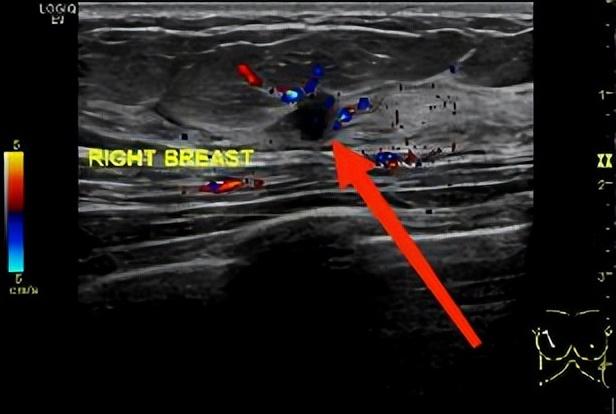

患者吴姐(化名)因为体检发现右侧乳房有结节4天来我院就诊,行乳腺超声检查,结果提示:右乳11点位结节,8.6×5.3mm,BI-RADS 4C(图1);乳腺MRI增强扫描示:右乳肿块,7×6mm大小,BI-RADS 5(图2)。

图1. 超声提示乳腺结节,红色箭头所指处为结节